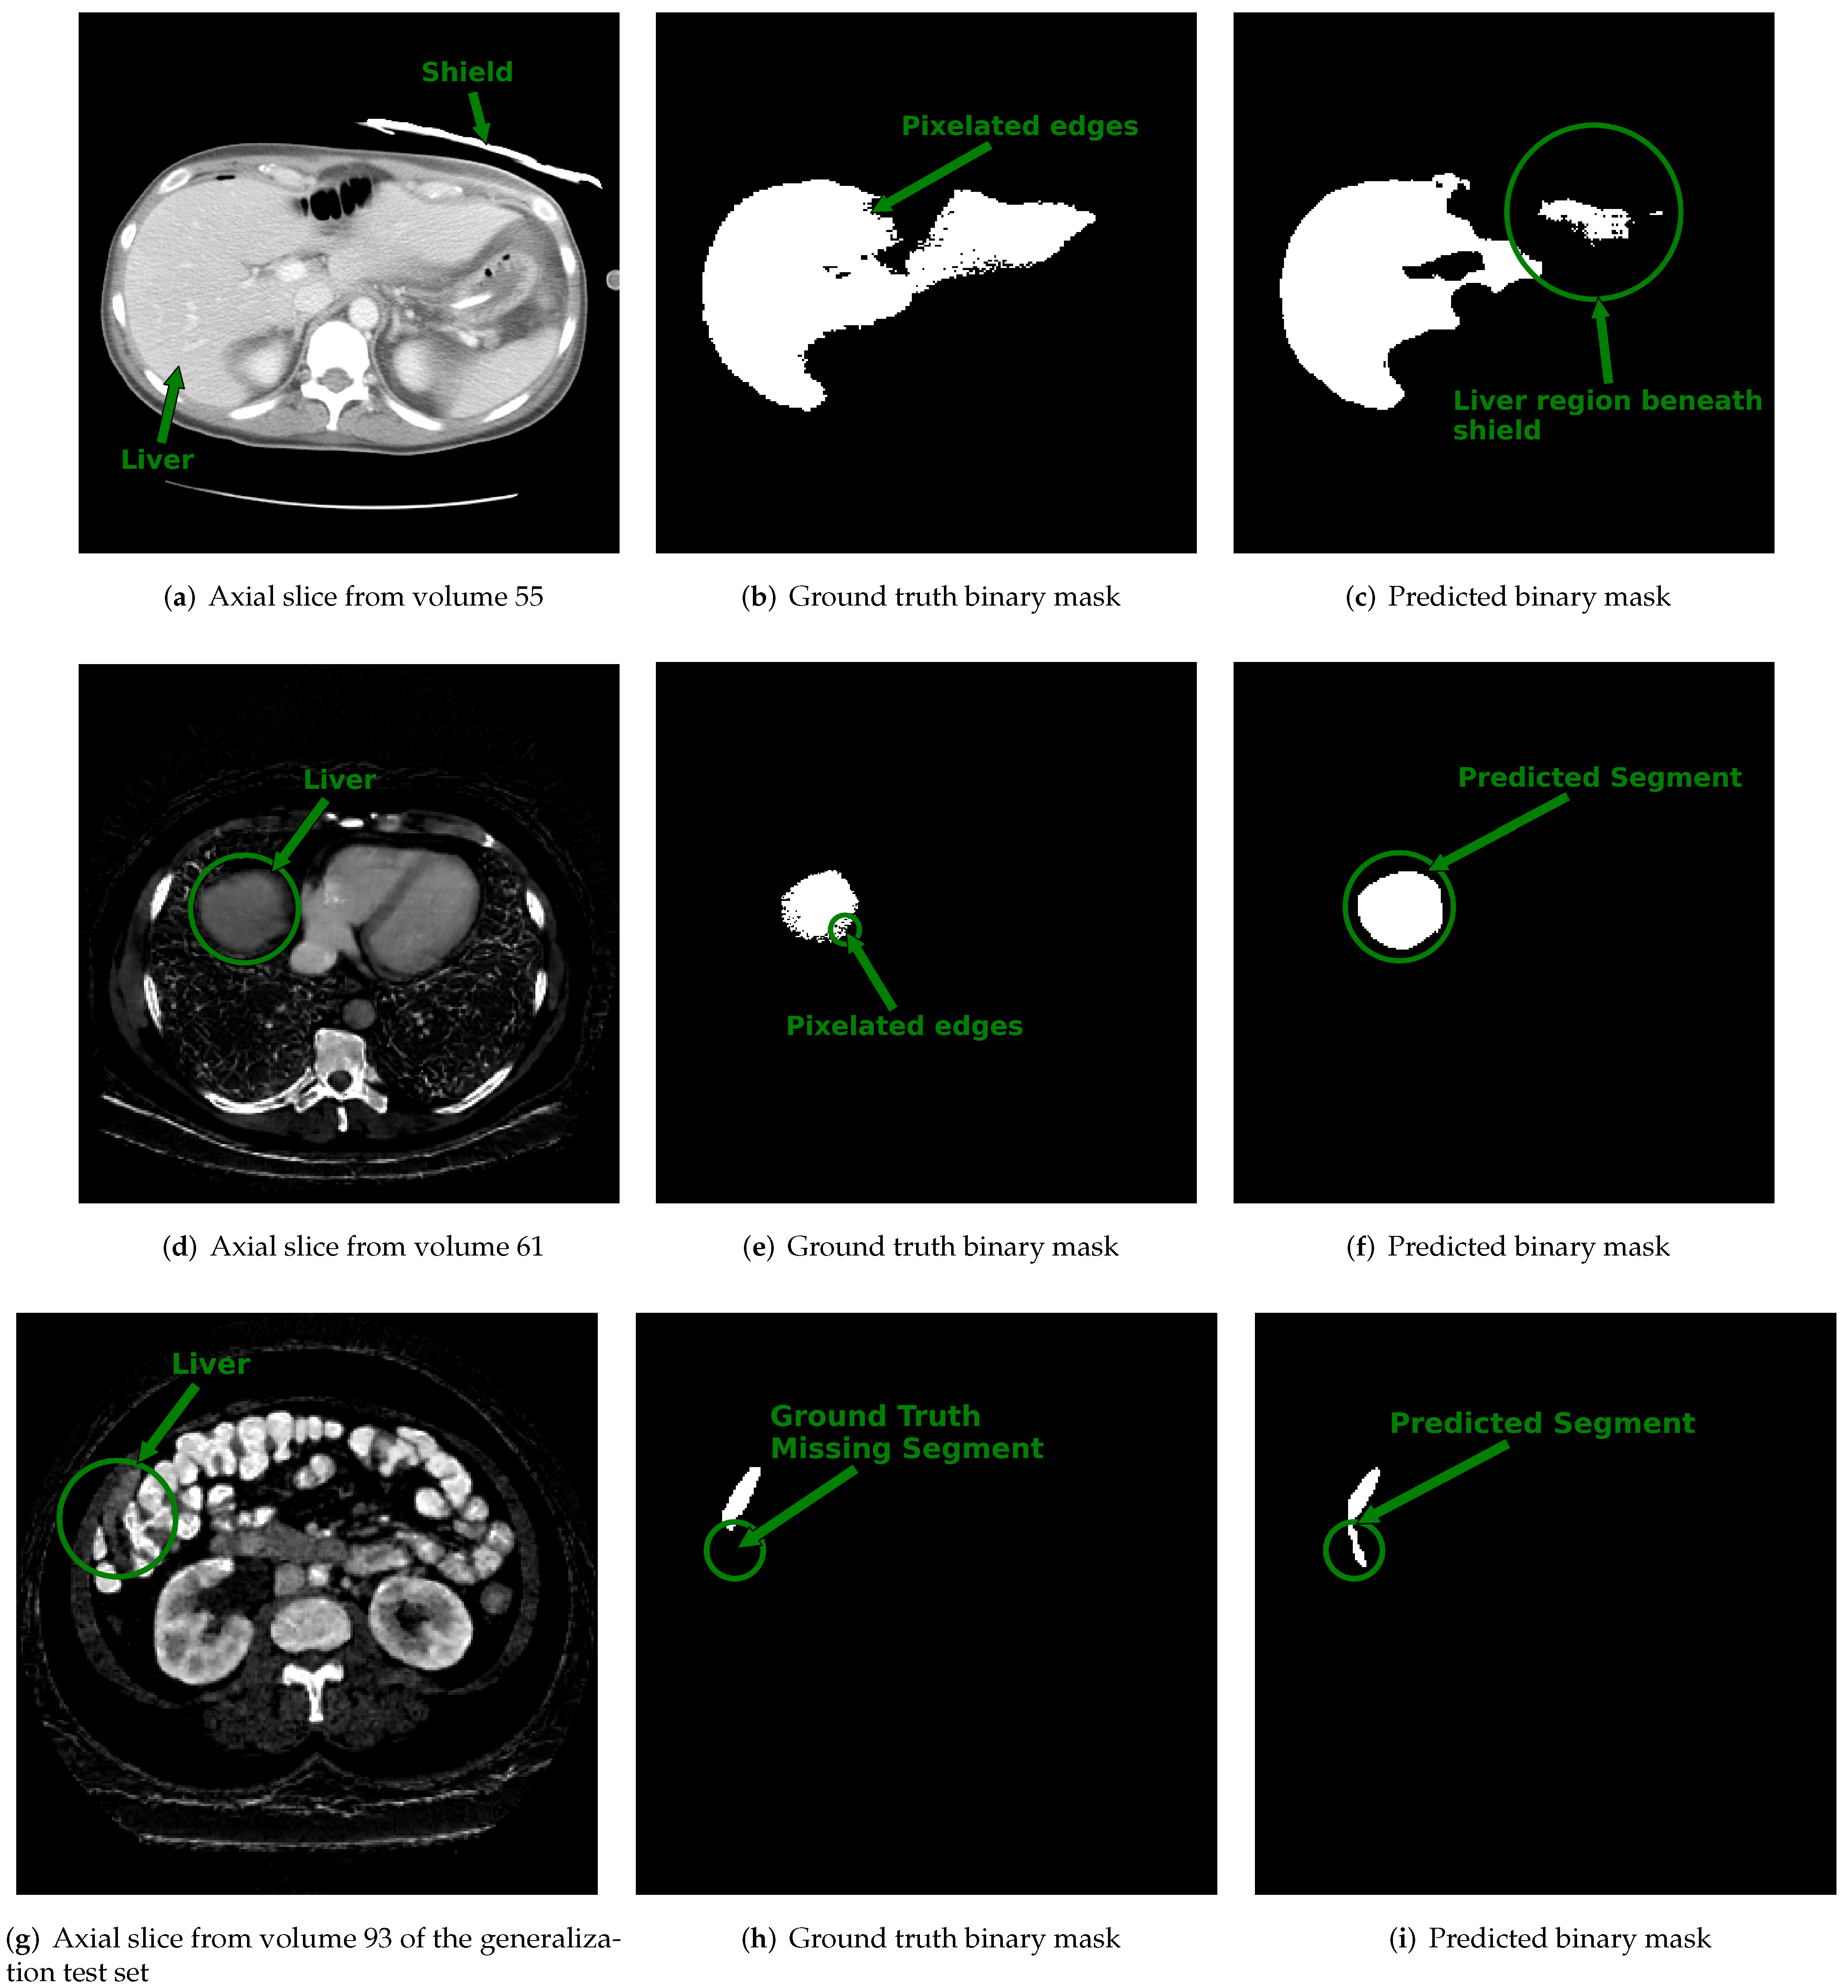

Figure 6. Displayed are example cross sectional axial slices with ground truth annotations and predicted contours from 3D u-net. Top Row: (a) Axial slice from single energy CT (SECT) scan of a patient within the CT-ORG training dataset shows an attenuating shield placed over segment 2 of the liver. (b) The ground truth binary image provided for the slice shown in (a) has pixelated edges pointed to by the arrow. (c) The output predicted by the 3D u-net for the slice in (a). The circled region pointed to by the arrow shows the area under the shield where the 3D u-net under-segmented the liver. Middle Row: (d) The synthetic dual-energy CT (synth-DECT) material density iodine (MDI) slice from a patient in the held-out test set. The liver is circled and pointed to by an arrow. (e) The ground truth binary image provided with the CT-ORG dataset for the slice shown in (d) also has pixelated edges that are circled and pointed to by the arrow. (f) The output predicted by the 3D u-net is circled and pointed to by the arrow. It incorporated the entire extent of the liver, without any pixelation. Bottom Row: (g) An axial slice from a patient scan in the generalization test set. The circled area and arrow point the portion of the liver at the margins of the liver. (h) The ground truth slice for the image shown in (g) does not contain a portion of the liver. The circle and arrow point to the segment of the liver missing from the ground truth annotation. (i) The predicted output by the 3D u-net. The circle and arrow point to the segment of the liver that was successfully identified by the 3D u-net, but was missing from the ground truth annotation shown in (h). The top row shows the impact of noise and beam hardening arising from the shield’s on the predictions of the 3D u-net. Several scans in the training dataset had ground truth contours with pixelated edges, missing segments of the liver, or inclusion of non-liver tissue, as shown in this figure.

Examples of slices from scans within the dataset with the lowest DSC values (i.e., DSC < 0.8) are displayed in Figure 6. Figure 6a shows the center slice of the liver, which is where the liver occupies around 50% or more of the abdominal space. In contrast, at the start and end slices, the liver tissue occupies a minor proportion of the abdominal area, as illustrated in Figure 6d,g. We suspect that the reduced DSC scores at the start and end slice locations are a byproduct of the small size of the liver tissue relative to the background and partial volume averaging artifacts that falsely reduce or increase the pixel intensity value of border pixels. Consequently, the class imbalance and artifacts at the margins of the scan may increase the likelihood of misclassifying pixels.

Additional factors that contributed to the lower DSC score are also illustrated in Figure 6. In Figure 6a, we found a case in which a bismuth or lead shield was placed over the patient’s abdomen during the scan. The shield attenuates X-rays, causing beam hardening and streak artifacts, as well as increasing noise in the organs beneath it. In addition to the shield, the ground truth annotation provided by the dataset organizers shown in Figure 6b contained pixelated edges. As shown in Figure 6c, the combined effect caused the 3D u-net to undersegment the portion of the liver directly under the shield. Figure 6d–f show an example slice with its ground truth contour that contains pixelated edges and the predicted output of the 3D u-net. In this case, the reduced DSC score was not a result of over or under segmentation by the 3D u-net but was, instead, due to the differences arising from the pixelation in the ground truth and lack thereof in the predicted output. In another example shown in the final row of Figure 6g–i, the reduced DSC score for this case was because the ground truth annotation displayed in Figure 6h did not outline the entire segment of the liver. However, as illustrated in Figure 6i, the predicted output of the 3D u-net included the full extent of the liver. Several scans in the CT-ORG dataset had ground truth annotations that were rough outlines of the liver or consisted of pixelated edges [45]. Despite imprecise ground truth contours, the 3D u-net trained using synth-DECT MDI scans was still able to predict the complete extent of the liver tissue for many patient scans.